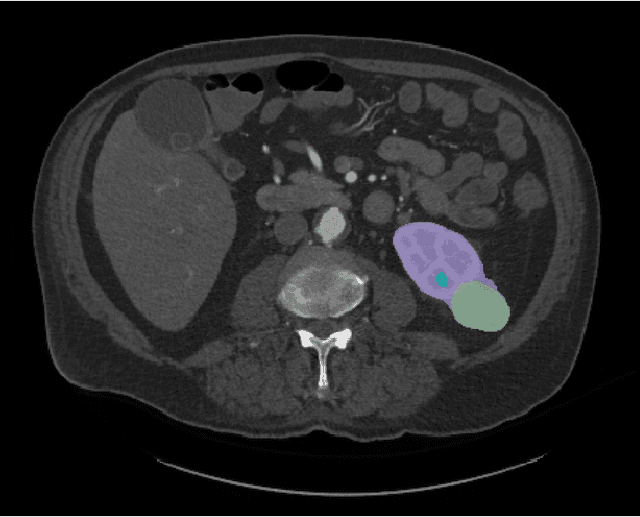

Abstract:Kidney cancer is a global health concern, and accurate assessment of patient frailty is crucial for optimizing surgical outcomes. This paper introduces AI Age Discrepancy, a novel metric derived from machine learning analysis of preoperative abdominal CT scans, as a potential indicator of frailty and postoperative risk in kidney cancer patients. This retrospective study of 599 patients from the 2023 Kidney Tumor Segmentation (KiTS) challenge dataset found that a higher AI Age Discrepancy is significantly associated with longer hospital stays and lower overall survival rates, independent of established factors. This suggests that AI Age Discrepancy may provide valuable insights into patient frailty and could thus inform clinical decision-making in kidney cancer treatment.

Abstract:This paper presents the challenge report for the 2021 Kidney and Kidney Tumor Segmentation Challenge (KiTS21) held in conjunction with the 2021 international conference on Medical Image Computing and Computer Assisted Interventions (MICCAI). KiTS21 is a sequel to its first edition in 2019, and it features a variety of innovations in how the challenge was designed, in addition to a larger dataset. A novel annotation method was used to collect three separate annotations for each region of interest, and these annotations were performed in a fully transparent setting using a web-based annotation tool. Further, the KiTS21 test set was collected from an outside institution, challenging participants to develop methods that generalize well to new populations. Nonetheless, the top-performing teams achieved a significant improvement over the state of the art set in 2019, and this performance is shown to inch ever closer to human-level performance. An in-depth meta-analysis is presented describing which methods were used and how they faired on the leaderboard, as well as the characteristics of which cases generally saw good performance, and which did not. Overall KiTS21 facilitated a significant advancement in the state of the art in kidney tumor segmentation, and provides useful insights that are applicable to the field of semantic segmentation as a whole.

Abstract:There is a large body of literature linking anatomic and geometric characteristics of kidney tumors to perioperative and oncologic outcomes. Semantic segmentation of these tumors and their host kidneys is a promising tool for quantitatively characterizing these lesions, but its adoption is limited due to the manual effort required to produce high-quality 3D segmentations of these structures. Recently, methods based on deep learning have shown excellent results in automatic 3D segmentation, but they require large datasets for training, and there remains little consensus on which methods perform best. The 2019 Kidney and Kidney Tumor Segmentation challenge (KiTS19) was a competition held in conjunction with the 2019 International Conference on Medical Image Computing and Computer Assisted Intervention (MICCAI) which sought to address these issues and stimulate progress on this automatic segmentation problem. A training set of 210 cross sectional CT images with kidney tumors was publicly released with corresponding semantic segmentation masks. 106 teams from five continents used this data to develop automated systems to predict the true segmentation masks on a test set of 90 CT images for which the corresponding ground truth segmentations were kept private. These predictions were scored and ranked according to their average So rensen-Dice coefficient between the kidney and tumor across all 90 cases. The winning team achieved a Dice of 0.974 for kidney and 0.851 for tumor, approaching the inter-annotator performance on kidney (0.983) but falling short on tumor (0.923). This challenge has now entered an "open leaderboard" phase where it serves as a challenging benchmark in 3D semantic segmentation.

Abstract:The morphometry of a kidney tumor revealed by contrast-enhanced Computed Tomography (CT) imaging is an important factor in clinical decision making surrounding the lesion's diagnosis and treatment. Quantitative study of the relationship between kidney tumor morphology and clinical outcomes is difficult due to data scarcity and the laborious nature of manually quantifying imaging predictors. Automatic semantic segmentation of kidneys and kidney tumors is a promising tool towards automatically quantifying a wide array of morphometric features, but no sizeable annotated dataset is currently available to train models for this task. We present the KiTS19 challenge dataset: A collection of multi-phase CT imaging, segmentation masks, and comprehensive clinical outcomes for 300 patients who underwent nephrectomy for kidney tumors at our center between 2010 and 2018. 210 (70%) of these patients were selected at random as the training set for the 2019 MICCAI KiTS Kidney Tumor Segmentation Challenge and have been released publicly. With the presence of clinical context and surgical outcomes, this data can serve not only for benchmarking semantic segmentation models, but also for developing and studying biomarkers which make use of the imaging and semantic segmentation masks.